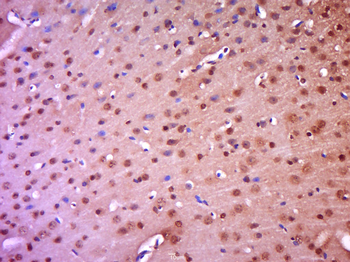

FC, ICC, IF, IHC-Fr, IHC-P, WB

Human, Mouse, Rat

Rat

Rabbit

Recombinant

Unconjugated

200 μl, 50 μl, 100 μl - Featured